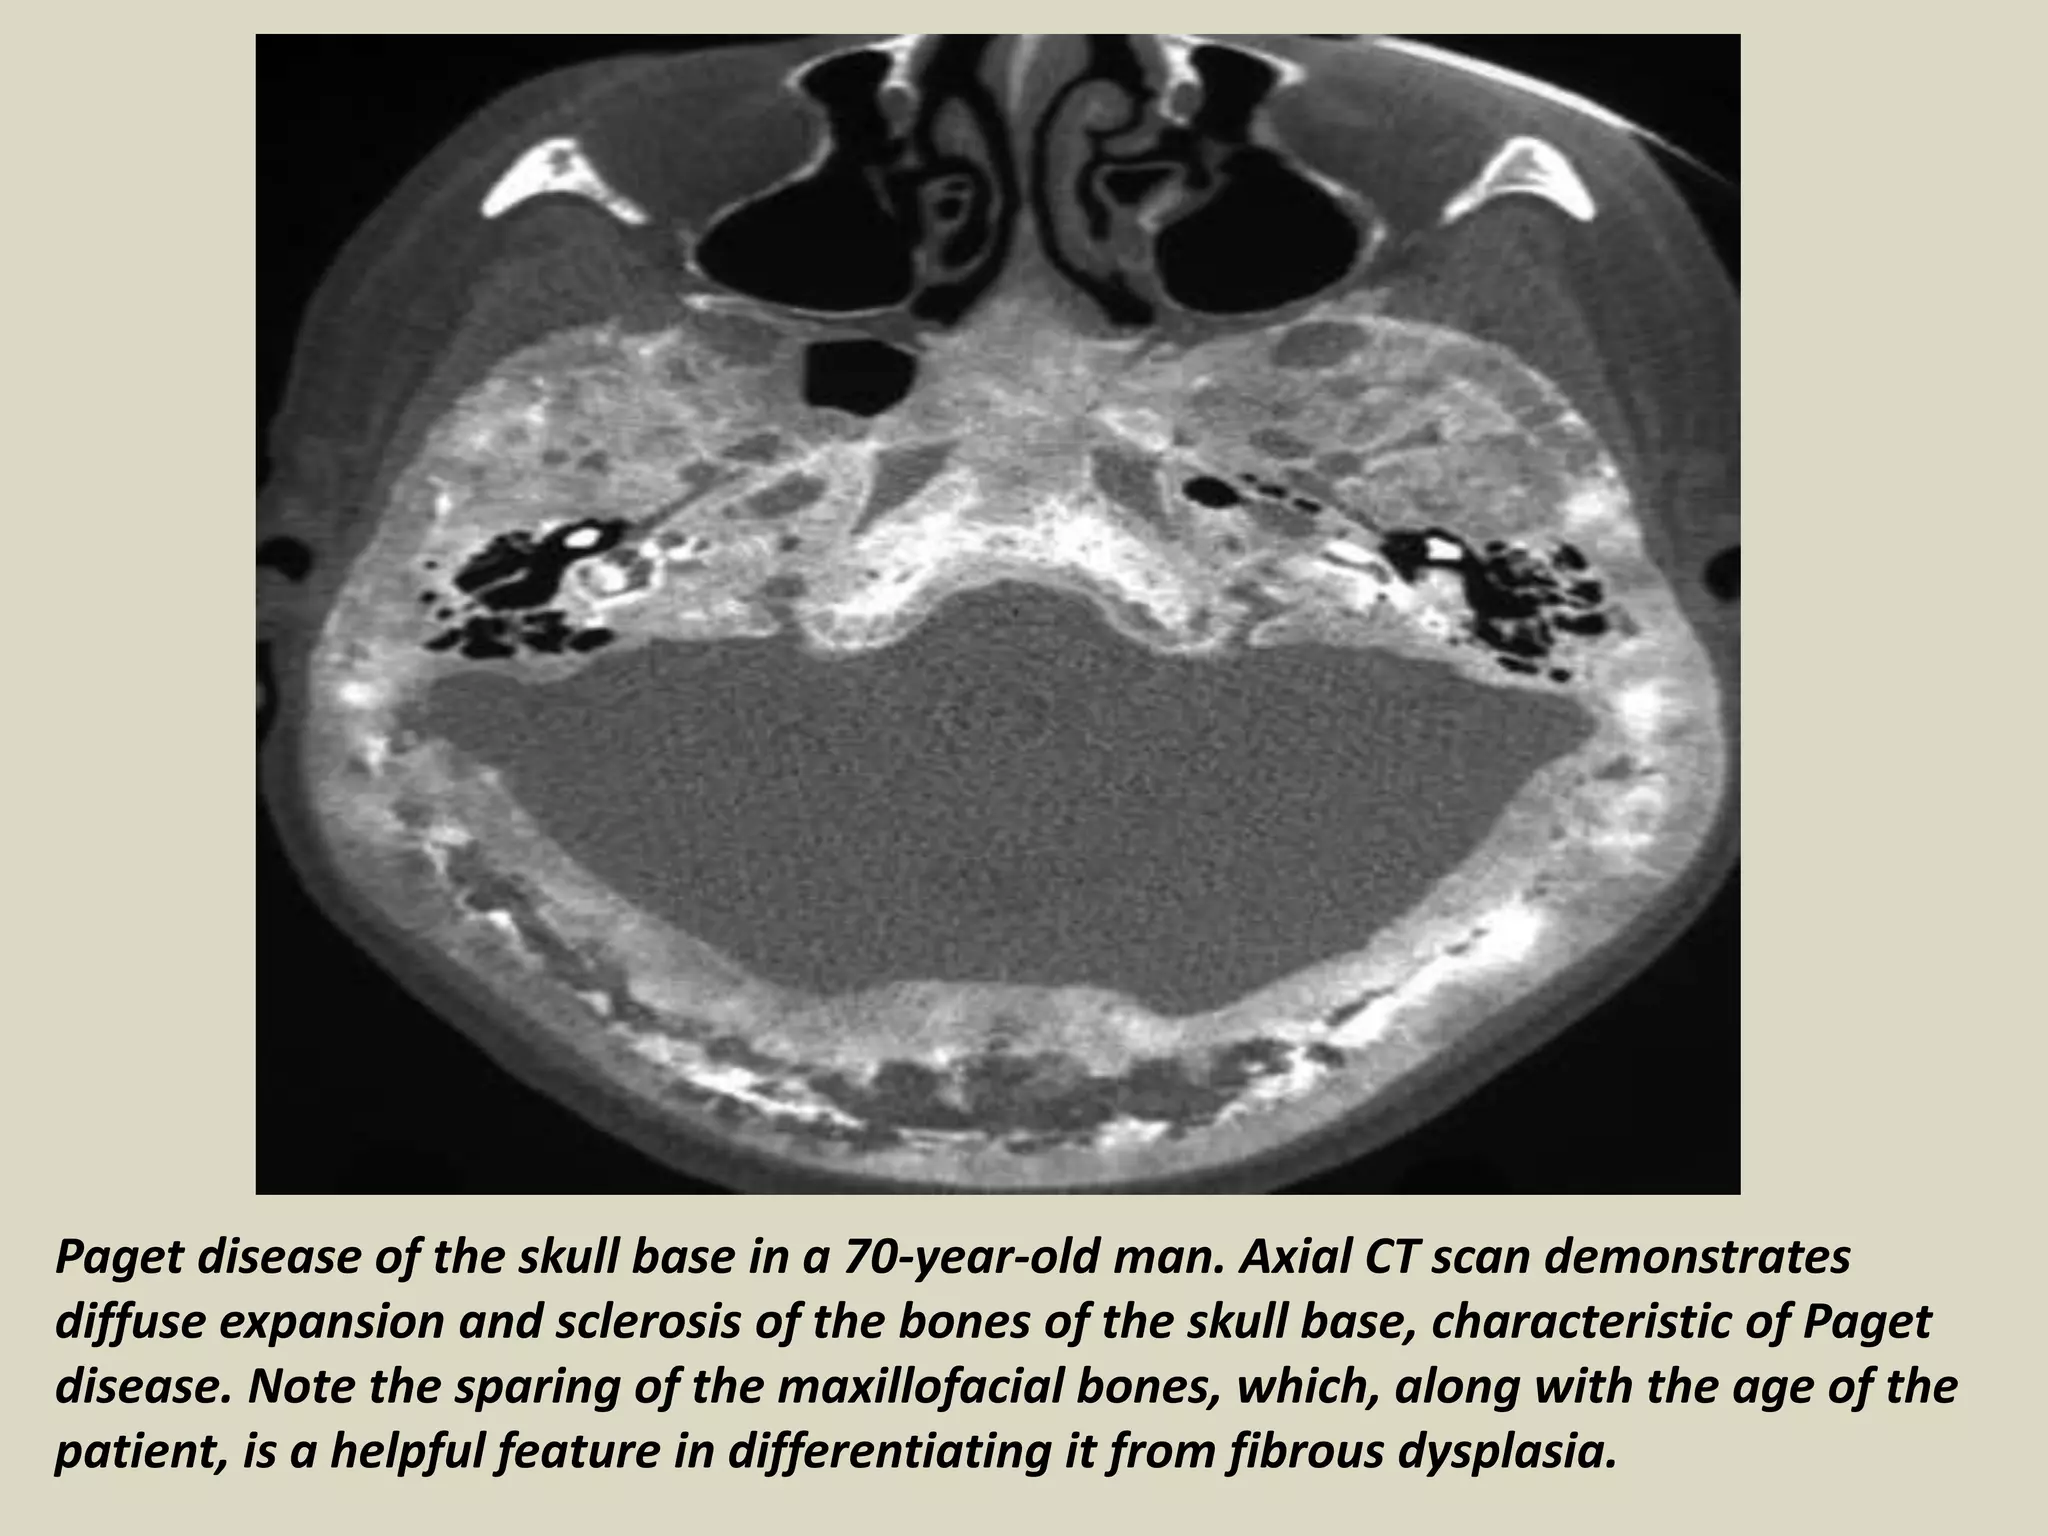

Paget disease of the skull base in a 70-year-old man. Axial CT scan demonstrates

diffuse expansion and sclerosis of the bones of the skull base, characteristic of Paget

disease. Note the sparing of the maxillofacial bones, which, along with the age of the

patient, is a helpful feature in differentiating it from fibrous dysplasia.